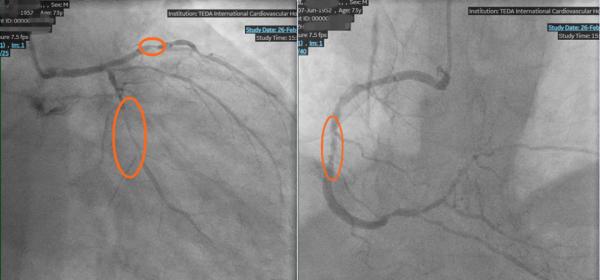

更棘手的是,周先生不仅有30年高血压、3年糖尿病史,长期的基础病让他的血管条件变得极差。冠脉造影结果更让人揪心:心脏的三根主要血管(前降支、回旋支、右冠状动脉)全部严重狭窄,最关键的生命线左前降支堵塞程度高达99%,随时可能因急性缺血引发心肌梗死甚至心脏骤停。这种三支病变叠加心功能极差的情况,属于典型的复杂、高危病变。患者合并症多,传统外科搭桥手术风险极高,常规介入手术也极易因血流波动引发心脏骤停等恶性事件,治疗一度陷入两难。

王永德主任团队利用宝贵的窗口期,凭借精湛技术,分别对堵塞严重的左前降支、左回旋支、右冠状动脉的多处严重狭窄病变部位进行球囊扩张和支架植入。

术后造影显示,原本几乎堵死的血管被成功打通,血流恢复通畅。周先生胸闷、憋气、夜间憋醒的症状彻底消失,精神状态也明显好转。